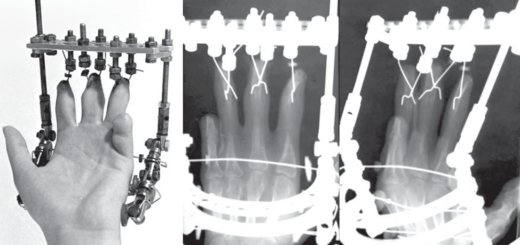

Technical note

After reviewing anatomical atlases and verifying in cadaveric specimens, we created a universal nomenclature system of muscles and applied it in the leg segment. The purpose of the proposed classification system of muscles is to briefly and visually characterize each muscle participating in lengthening of this segment in terms of the consequences for both the muscle itself and changes in the biomechanical conditions of its operation. The coding of muscles is designed so that it would be possible, without referring to any literature or atlases, to clarify the anatomy and topography of a particular muscle, and also to understand the nature of its involvement in lengthening the tibia.